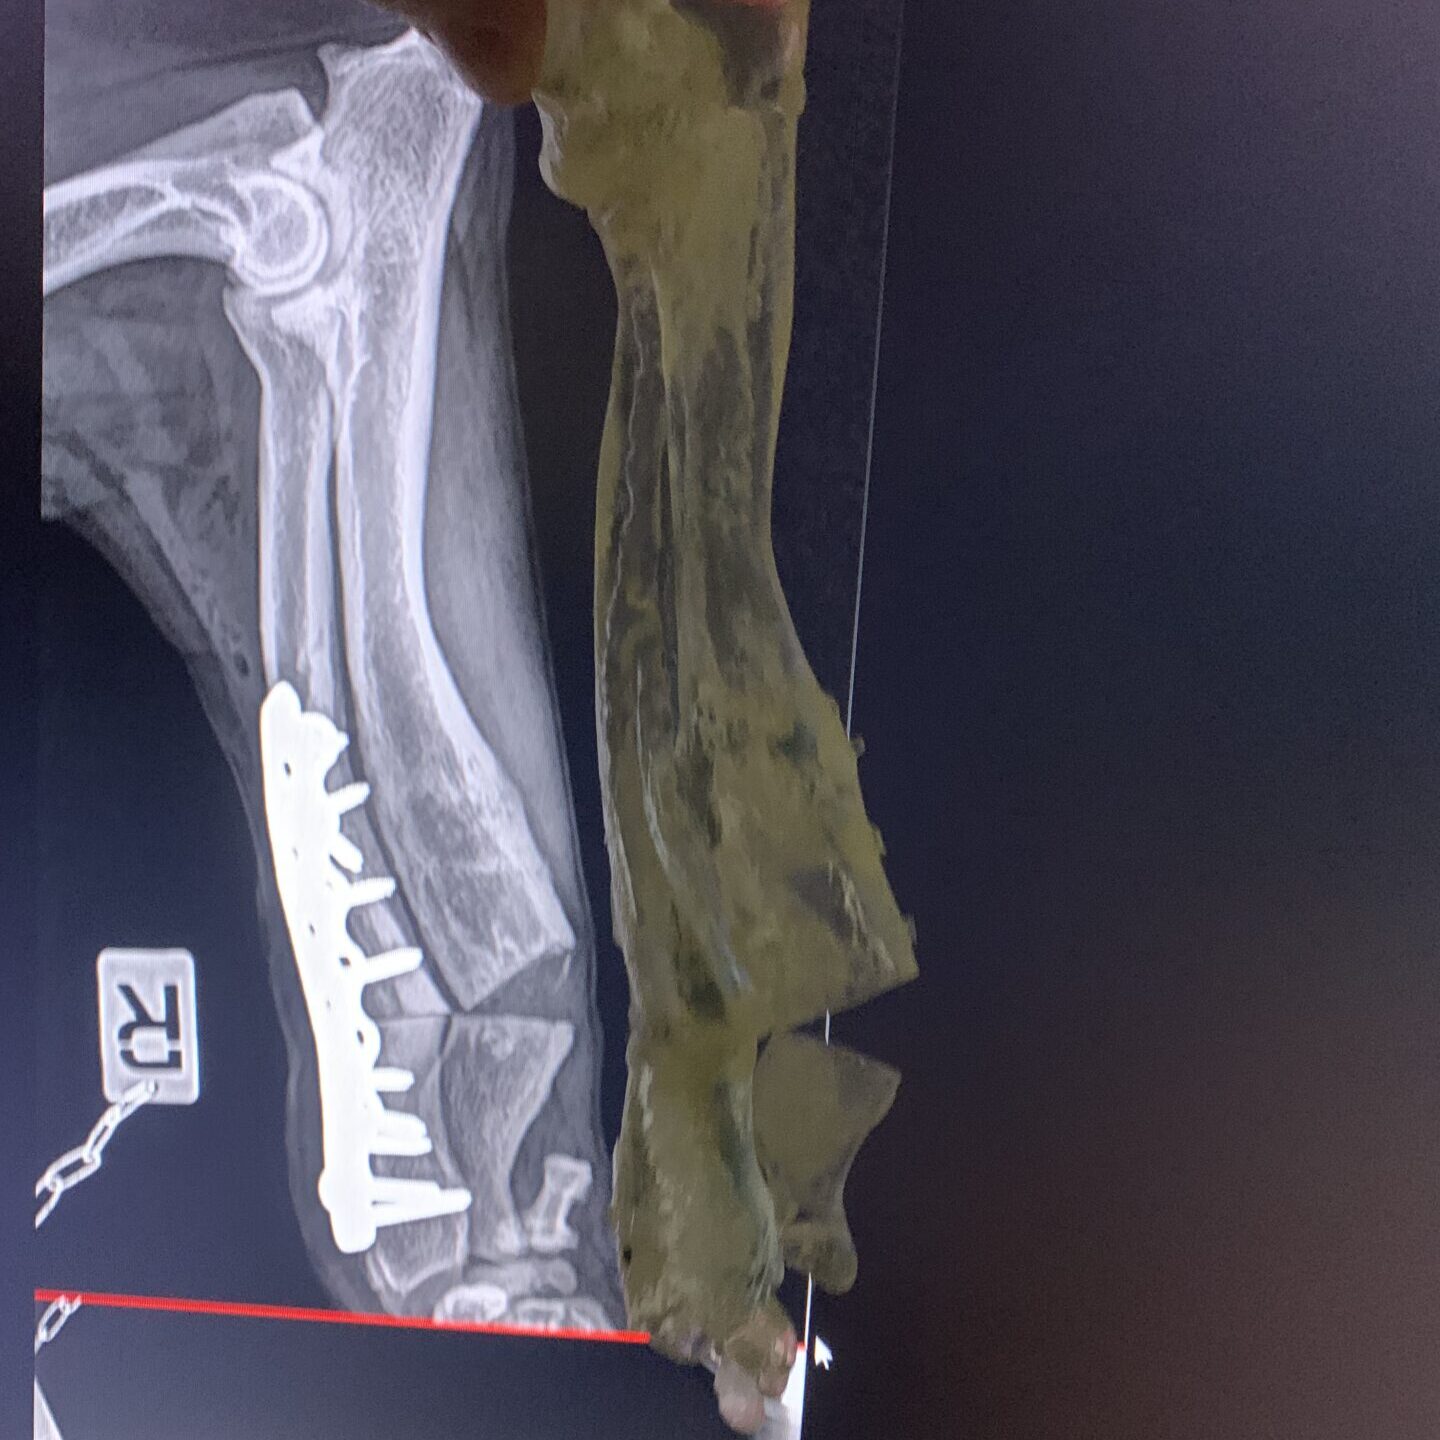

- CT scanning can give high-resolution, three-dimensional images of the bones and joints. It is a powerful tool for detecting and measuring all types of bone deformity and joint incongruity, and for advanced surgical planning.

- Corrective osteotomies. It might be necessary to reduce the bends and/ or twists in the bone to improve limb function. This is generally done by cutting the effected bones, adjusting their shape, and fixing them in place while they heal. We might advise having patient-specific custom surgical guides made. We would usually aim to stabilise the bones with internal implants (e.g. bone plates) to make the post-operative care easier.

Premature closure of antebrachial growth plates

The most common site for growth deformities is the antebrachium. This is because the radius and ulna must grow at the same rate. 85% of the growth of the ulna comes from the distal growth plate and so it is not surprising that the most common growth problem is premature closure of the distal ulnar growth plate. This causes the ulna to act as a ‘bow string’ on the radius and the radius can start to bow (“radius curvus”). Treatment of this problem can take various forms often depending on the age of the puppy. Careful evaluation, planning and monitoring is necessary for best outcomes. If the problem is caught early, sometimes it is possible to influence growth to reduce the deformity. In other cases, it may be necessary to perform corrective surgery to acutely correct the deformity, and in other cases a gradual correction may be performed using external frames and pins.

The pictures here are of a Flat-Coat Retriever who had growth deformities in both legs.